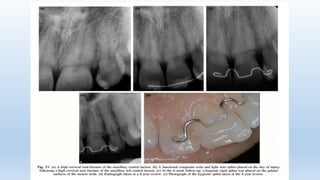

Before removal of a splint a radiograph should be taken. If there are

radiographic signs of periodontal breakdown, additional splinting

time is necessary (usually 3–4 weeks)

• Root fractures can be located in the apical, middle or cervical third of the root.

Displacement of the coronal fragment can be classified as concussion,

subluxation, extrusion and lateral luxation.

• Root fractures in the apical third of the root and without coronal fragment

displacement do not normally require any splint.

Based on controversial results in recent studies, it has been recommended

to splint root fractures located at mid‐root for 4 weeks.

• In cervical root fractures, a longer splinting time might be indicated.